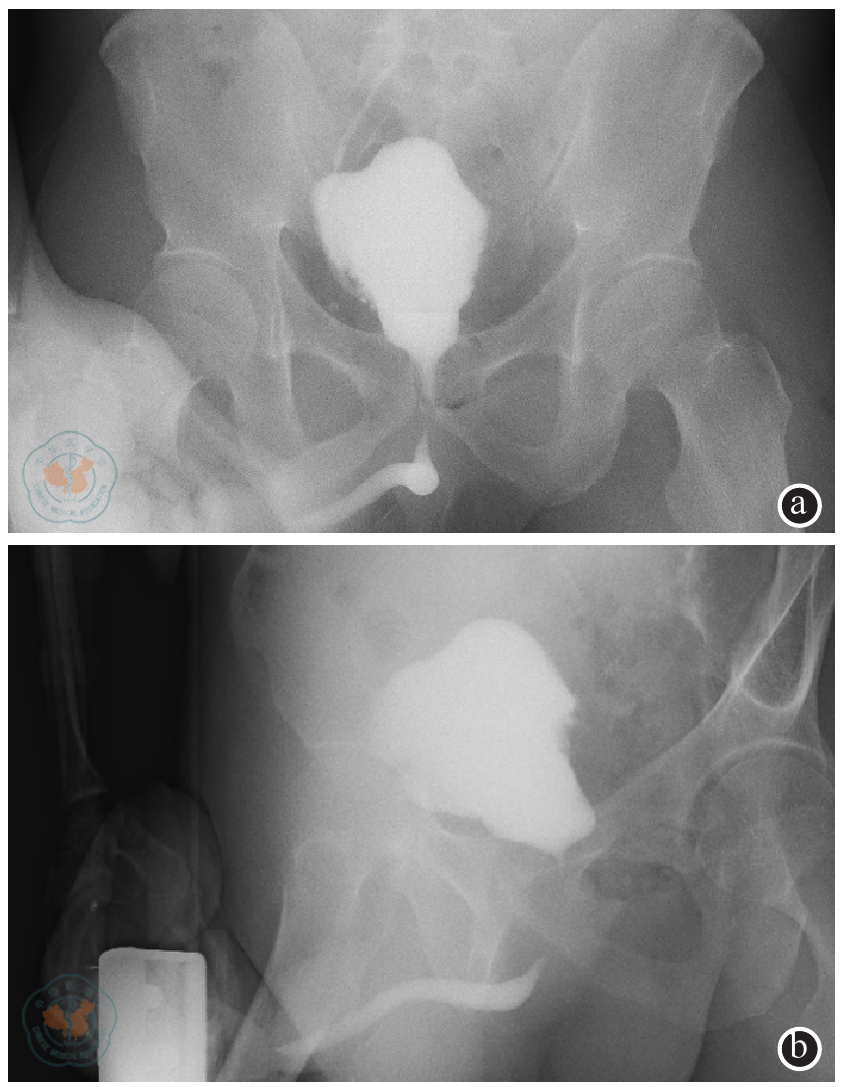

图1 氯胺酮相关性膀胱炎患者术前膀胱造影注:膀胱壁不光滑,膀胱重度挛缩(图a和b分别为腹部正位片和侧位片)